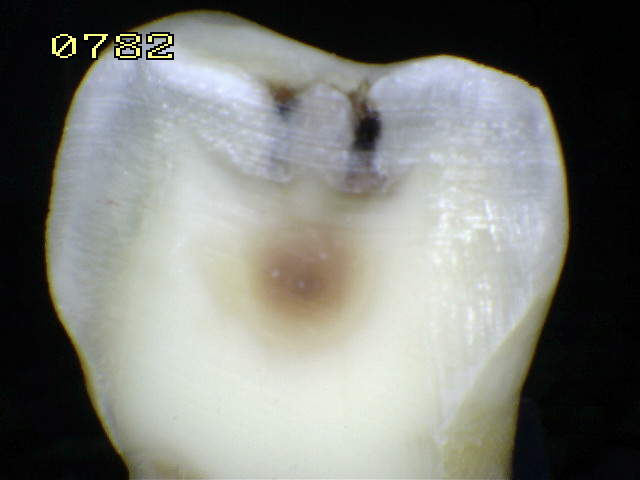

Espécimen Nº 50 |

|

| Corte sagital |

Código histológico 3 |